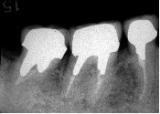

歯槽膿漏・X線写真 | ||

| 歯槽膿漏によって失われた骨(→印の部分)が再生しています。 | ![]() |

![]() |

【術前】 |

【術後】 |